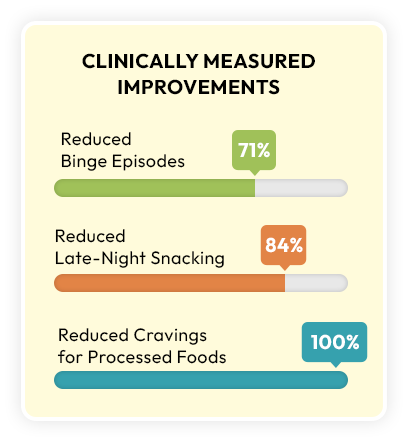

In one study, this strain reduced binge episodes by 71%...

Late-night snacking by 84%...

And reduce cravings for processed foods.